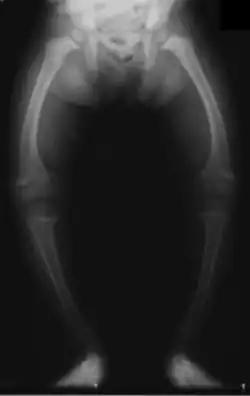

| X-ray of a two-year-old with rickets, demonstrating a marked bowing of the femurs and decreased bone density | |

An X-ray or radiograph of an advanced patient with rickets tends to present in a classic way: the bowed legs (outward curve of long bones of the legs) and a deformed chest. Changes in the skull also occur, causing a distinctive "square-headed" appearance known as "caput quadratum".[18] These deformities persist into adult life if not treated. Long-term consequences include permanent curvatures or disfiguration of the long bones, and a curved back.[19]